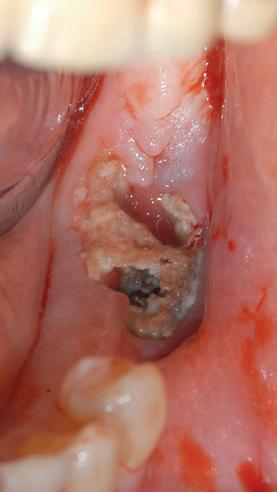

avancés, la sclérose s'étend à des parties plus importantes de l'os maxillaire. Si l'os s'infecte, cela peut entraîner une ostéolyse, la formation de séquestres et de fistules, voire une fracture pathologique. Dans le cas de la DIONJ avancée (à partir du stade 1), l'os maxillaire est exposé en un ou plusieurs endroits de la cavité buccale (illustrations 2 et 3). Les patient-e-s

peuvent alors être largement asymptomatique ou ressentir des douleurs faibles à fortes. L'ampleur des douleurs dépend principalement de l'étendue de la nécrose et d'une éventuelle inflammation concomitante (stade 2) ou d'autres complications (stade 3) (illustrations 4 et 5).

Patiente ayant suivi un traitement de 3 ans par pamidronate (Aredia®) pour un cancer du sein métastatique. Après la pose d'un implant dans la mâchoire inférieure, une ostéonécrose s'est formée autour de l'un des implants, ce qui a entraîné plus tard la perte de l'implant (stade 2).

Abbildung 3:

Patientin mit 3-jähriger Therapie mit Pamidronat (Aredia®) wegen einer metastasierenden Brustkrebserkrankung. Nach der Implantatversorgung im Unterkiefer bildete sich eine Osteonekrose um das eine Implantat, was später zum Implantatverlust führte (Stadium 2).